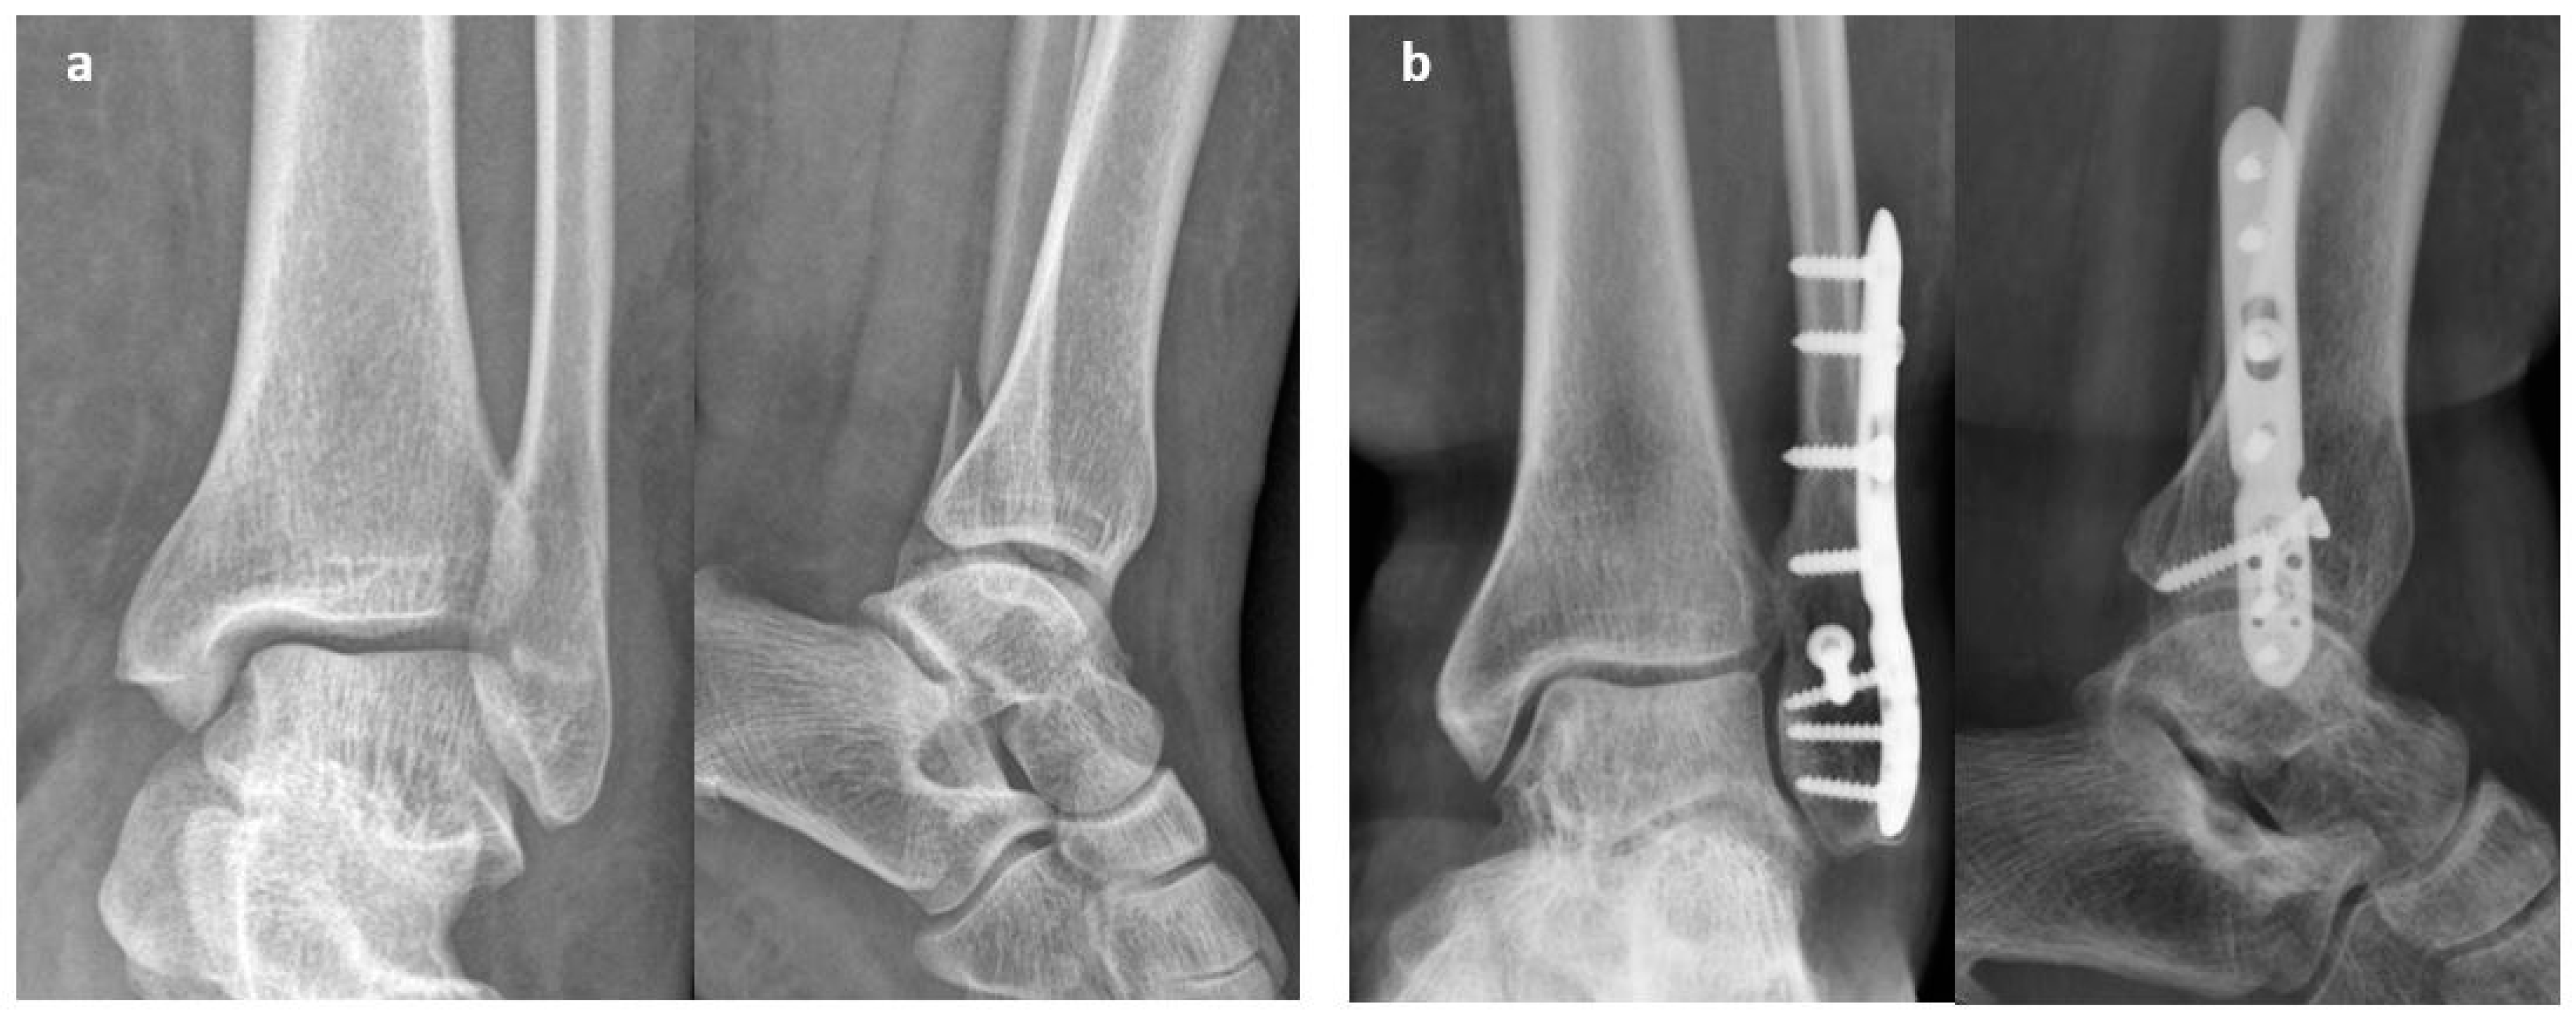

2.1. Surgical Procedure